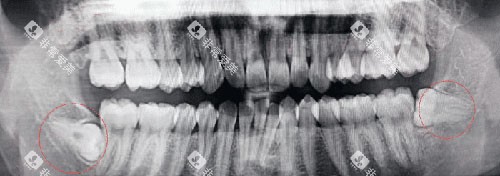

智齿位置:上颌智齿离神经线远,拔起来相对简单;下颌智齿靠近神经线,尤其是阻生智齿,可能还要切开牙龈、去骨,难度翻倍。

生长情况:正位智齿长得规规矩矩,拔起来轻松;阻生智齿(比如横着长、斜着长)就像“钉子户”,医生得费大力气才能搞定。

下颌智齿因为位置深、靠近神经线,拔除难度比上颌大得多,价格自然也更高。具体分类如下:

下颌完全阻生智齿拔除:800到1500元/颗

特点:智齿完全埋在骨头里,拔除需要更复杂的操作。

适用人群:智齿完全未萌出,需要切开牙龈、去骨才能拔除。

下颌高位阻生智齿:1000元起,靠近神经线,风险高。

水平阻生智齿:1500元/颗起,需要更精细的操作。

舌侧阻生智齿:8000元起,因为位置刁钻,拔除难度极大。

拔除难度大:阻生智齿位置深、靠近神经线,拔除时稍有不慎就可能损伤神经,医生需要更谨慎、更精细的操作。